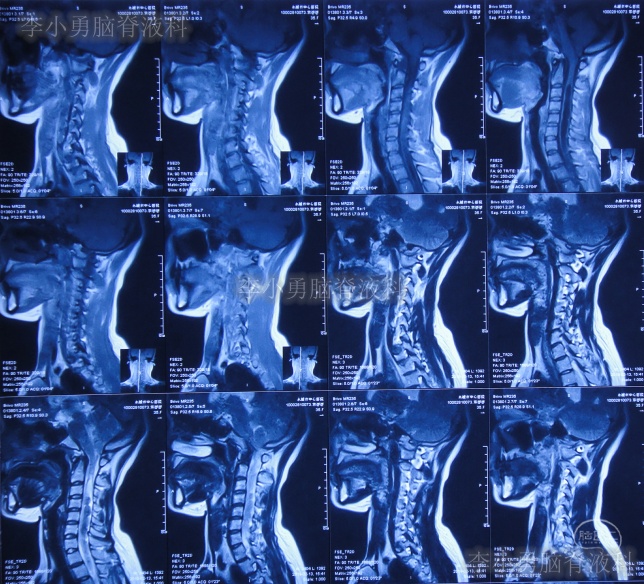

患者2019年2月初,因数次出现发作性黑蒙,2019年2月10日就诊于当地的河南省永城市某医院,查头颅CT未见明显异常(图-1);次日再查头颅核磁、颈椎核磁(图-2、图-3)后发现小脑扁桃体下疝畸形合并脊髓空洞。

图-3:2019年2月13日头颅核磁

小脑扁桃体下疝减压术后20天即2019年3月6日,查头颅、颈椎核磁发现仍有脊髓空洞(图-8、图-9)。

图-9:2019年3月6日头颅核磁